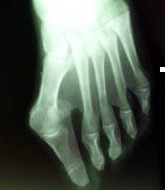

E’ caratterizzato dalla deformità del primo dito, comporta una deviazione laterale della falange. Con l’eventuale lussazione dei sesamoidi, due ossa che si trovano nell’articolazione dell’alluce. In pratica l’alluce valgo è una deformazione del piede che consiste nell’allontanamento dalla testa del primo metatarso dalle altre.

Il primo metatarso e l’alluce non sono più allineati ma formano tra loro un angolo detto valgismo. Da qui il nome a questa forma di deformità.

L’elemento che colpisce di più in questa patologia è l’alluce deformato, in realtà la causa e l’origine di questa malattia è un’altra. La cipolla, è costituita dalla sporgenza della testa del metatarso, il primo metatarso si sposta verso l’interno e si allontana dal secondo. L’alluce si trova senza base d’appoggio e cade nello spazio tra i due metatarsi. Questa è la deviazione in senso laterale, dà il nome all’alluce valgo.